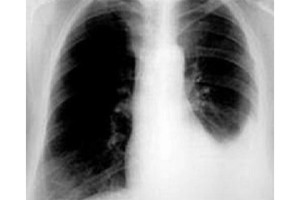

- Tiếp theo, bệnh nhân sẽ được các bác sĩ tiến hành đo điện tâm đồ, chụp X-quang ngực để xác định chính xác mức độ tổn thương của tim.